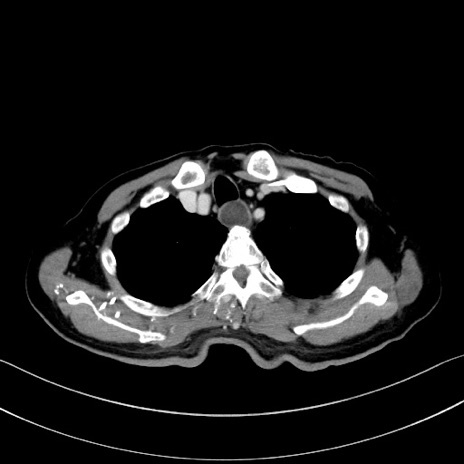

冠状断像

【症例】60歳代男性

【現病歴】胃癌にて胃全摘後。食思不振が悪化し、夜中に嘔吐することがある。

【既往歴】胃癌、胃全摘、脾摘、胆摘後

【データ】WBC 5900、CRP 10.56